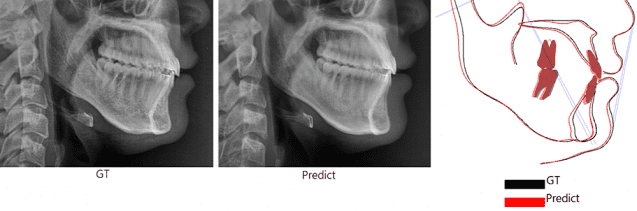

‘양악수술 후 내 모습’ 미리 보여주는 AI 모델 개발

[지디넷코리아] 서울아산병원 김남국 교수 “정밀한 치료 계획 수립, 환자 신뢰도 향상에 도움 될 것” 인공지능(AI)을 활용해 양악수술 후의 모습을 미리 보여주는 방사선 영상을 생성하는 기술이 최근 개발됐다. 악교정수술(양악수술)은 […]